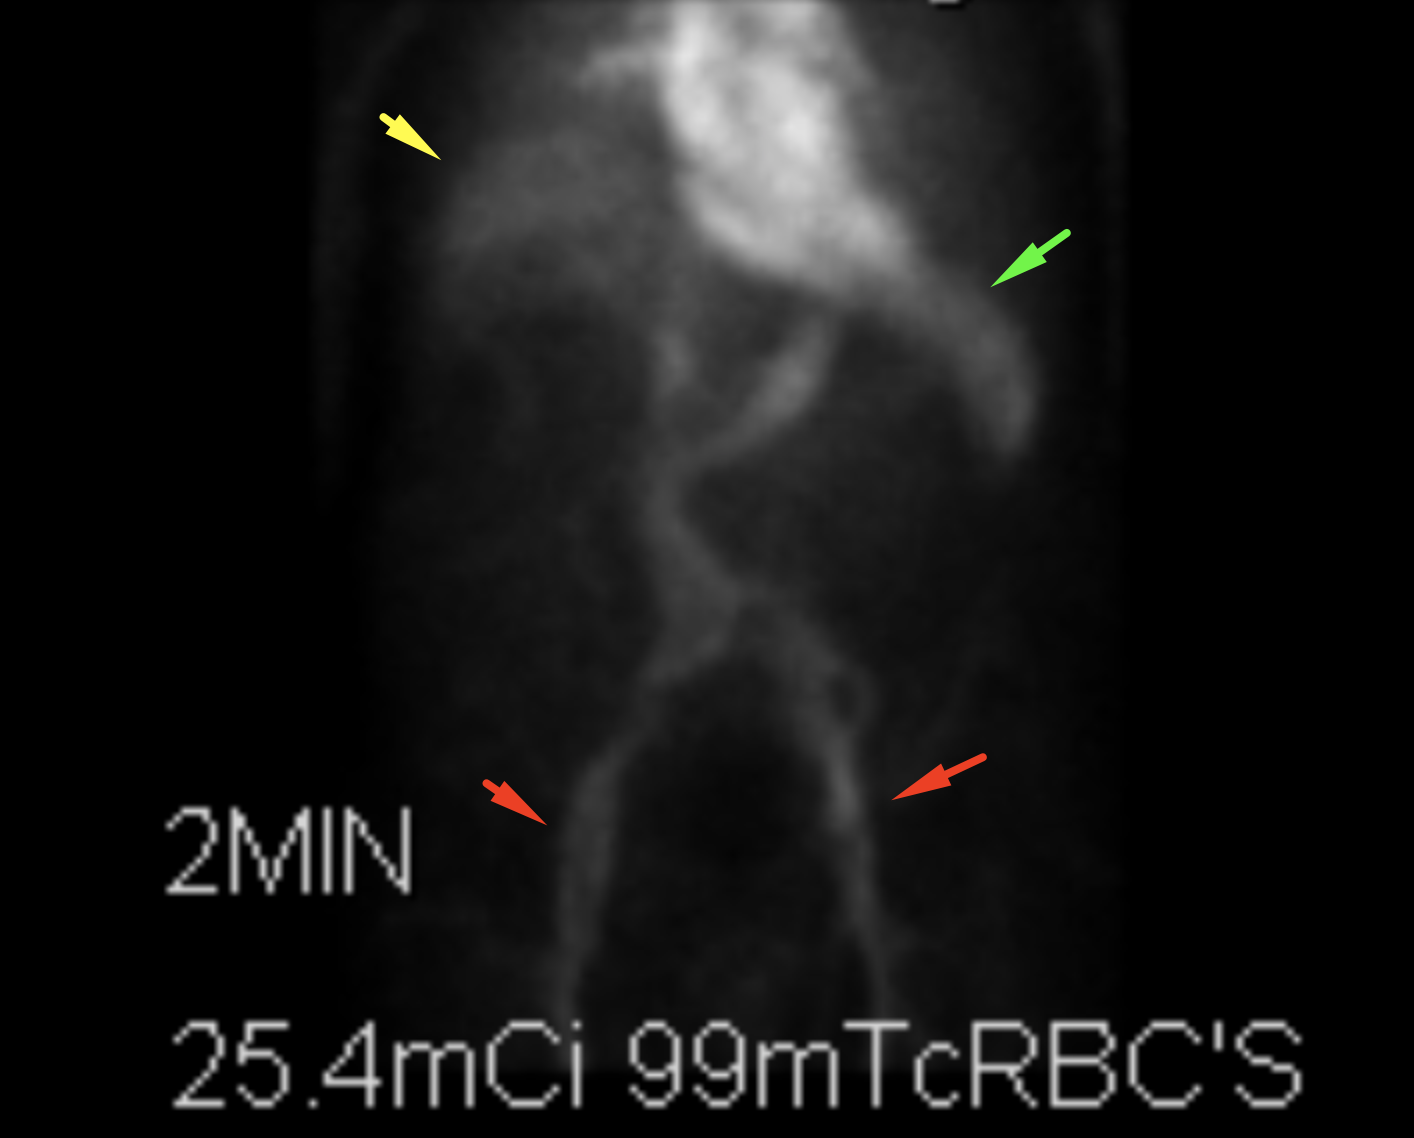

Age: 92

Sex: Male

Indication: Hematochezia

Radiotracer: Tc99m labeled RBCs

Sample ReportPositive for active GI bleed, likely originating in the hepatic flexure of the colon.